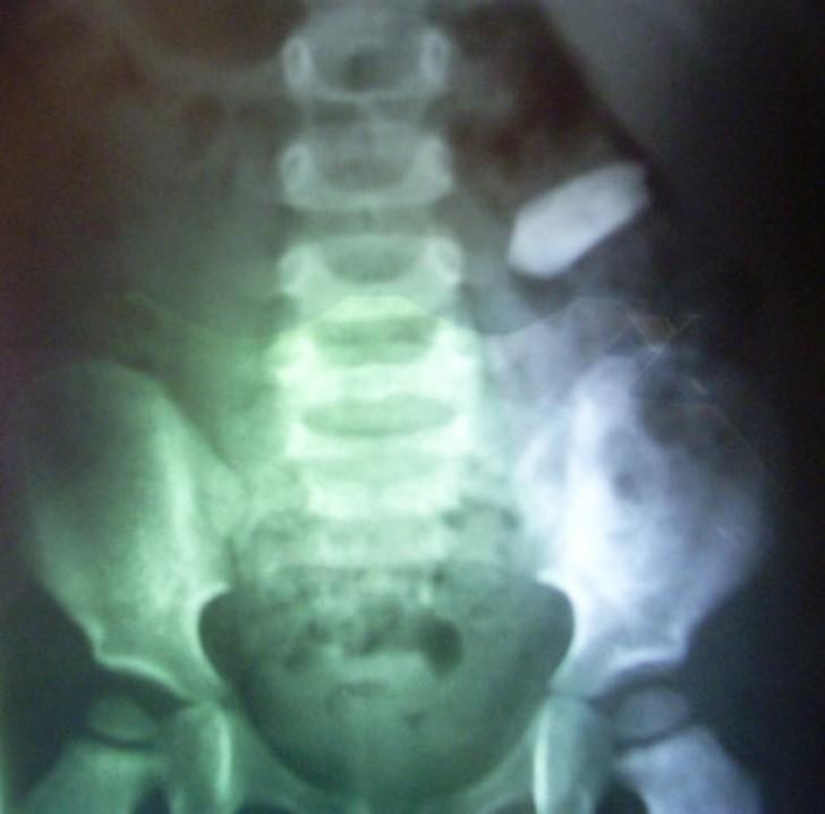

Botella.